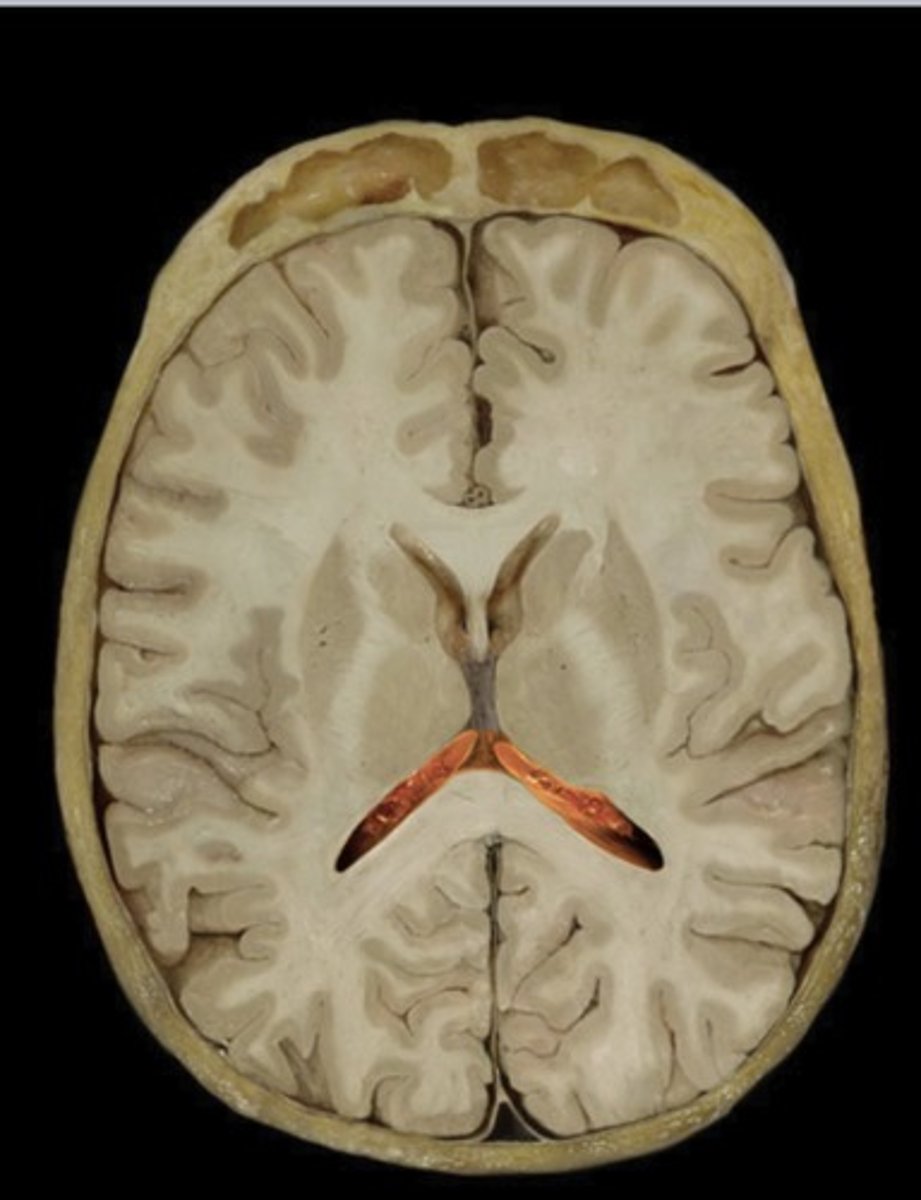

Third Ventricle

Name this structure

Fourth Ventricle

Name this structure

Occipital Lobe (transverse section)

Name this structure

Temporal Lobe (transverse section)

Name this structure

Thalamus (transverse section)

Name this structure

Gray matter

Name this structure

White matter

Name this structure